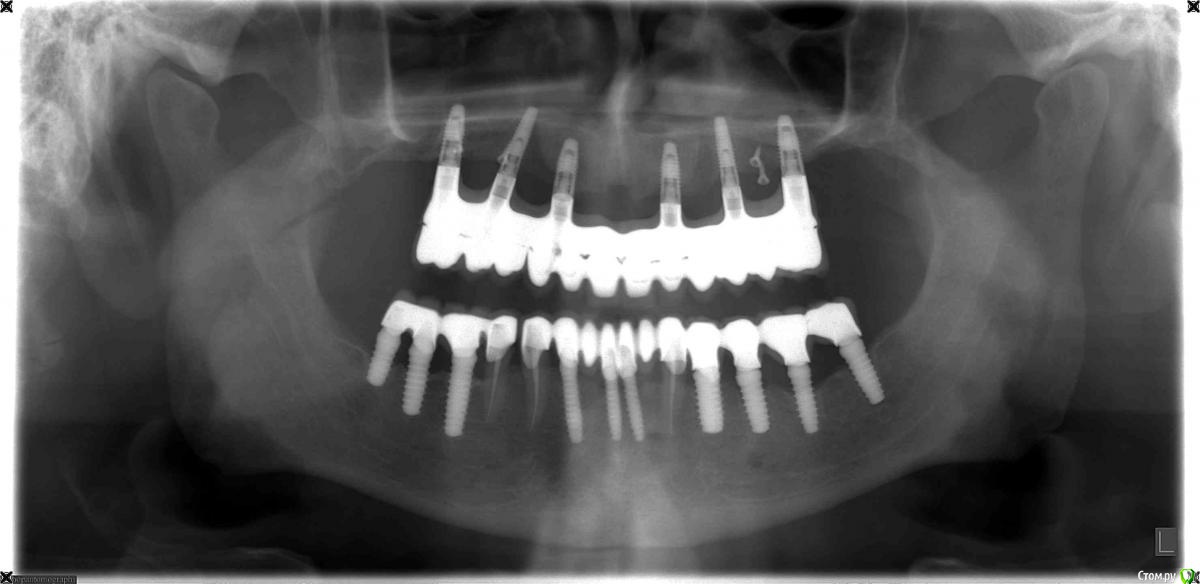

SergeyAL Опубликовано 11 сентября, 2015 Автор Поделиться Опубликовано 11 сентября, 2015 на первом этапе была проведена костная пластика по Кури в 1 и 2 квадрантах + двухсторонний синуслифт, доступ вертикальный тоннель. врменная реставрация на остатках зубов во фронтальном отделе.через 5 месяцев зубы подвели, пришлось проводить удаление зубов, одномоментную имплантацию, установку временных имплантатов во фронтальнос участке и фиксировать временную конструкцию на временных имплантатах.через 4 месяцараскрытие имплантатов с пластикой кератинизированной десны СДТвременное протезирование на постоянных имплантатахчерез 3 месяца постоянное протезирование на имплантатах последний снимок через 8 месяцев после постоянного протезирования. 4 Ссылка на комментарий

doca Опубликовано 11 сентября, 2015 Поделиться Опубликовано 11 сентября, 2015 А что там с костью? http://s017.radikal.ru/i409/1509/5e/e6057dfbde78.jpg 1 Ссылка на комментарий

Bier Опубликовано 11 сентября, 2015 Поделиться Опубликовано 11 сентября, 2015 я так понимаю, что это аугментат Ссылка на комментарий

doca Опубликовано 11 сентября, 2015 Поделиться Опубликовано 11 сентября, 2015 я так понимаю, что это аугментатбольше похоже на резорбцию, особенно ,учитывая,что там как раз был миниимплант Ссылка на комментарий

SergeyAL Опубликовано 11 сентября, 2015 Автор Поделиться Опубликовано 11 сентября, 2015 это область аугментации, отделяемого нет, карман не зондируется. область молодой костной ткани часто выглядит менее рентгеноконтрастной Ссылка на комментарий